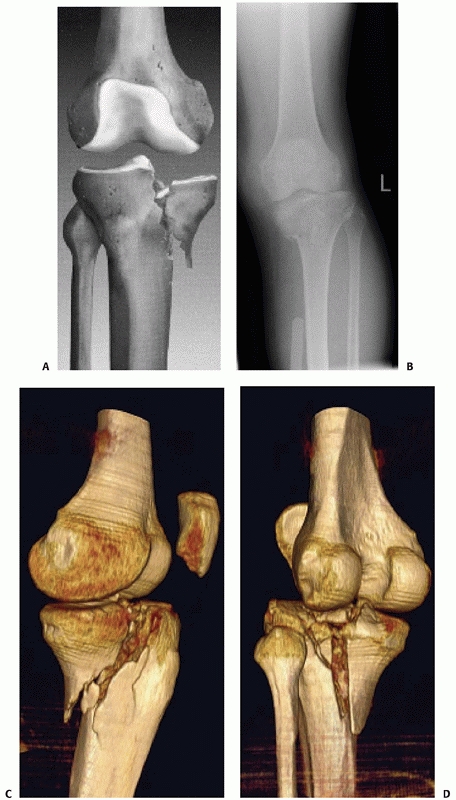

fracture lines or degree of displacement but are not routine. CT scans

have largely supplanted the need for these adjunctive views. When there

is substantial fracture displacement, particularly in bicondylar or

fracture dislocation patterns, radiographs in traction will better

assess the fracture anatomy (Fig. 53-5).

Traction restores the gross geometry of the proximal tibia, decreases

overlap, and better defines the fracture pattern than the original

radiographs. Manual traction may be applied solely for the purposes of

such radiographs, but in severe fractures, radiographs obtained after

applying a joint-spanning external fixator will provide the necessary

traction for assessment of fracture anatomy. When applying the fixator,

care should be taken to avoid having metal bars or clamps overlying the

proximal tibia in the plane of the important radiographic views.

![]() |

FIGURE 53-5

Advantages of traction in realigning a fractured tibial plateau. Distraction allows better imaging and facilitates fixing the fracture. The initial anteroposterior (AP) (A) and lateral (B) images show a severe fracture but little additional information can be gained because of the malalignment and overlap. C. An AP film after distraction with a spanning fixator dramatically improves the ability to assess this injury. D. A single screw was placed between the condyles, and 10 days later, the fracture was treated with a locking plate. |